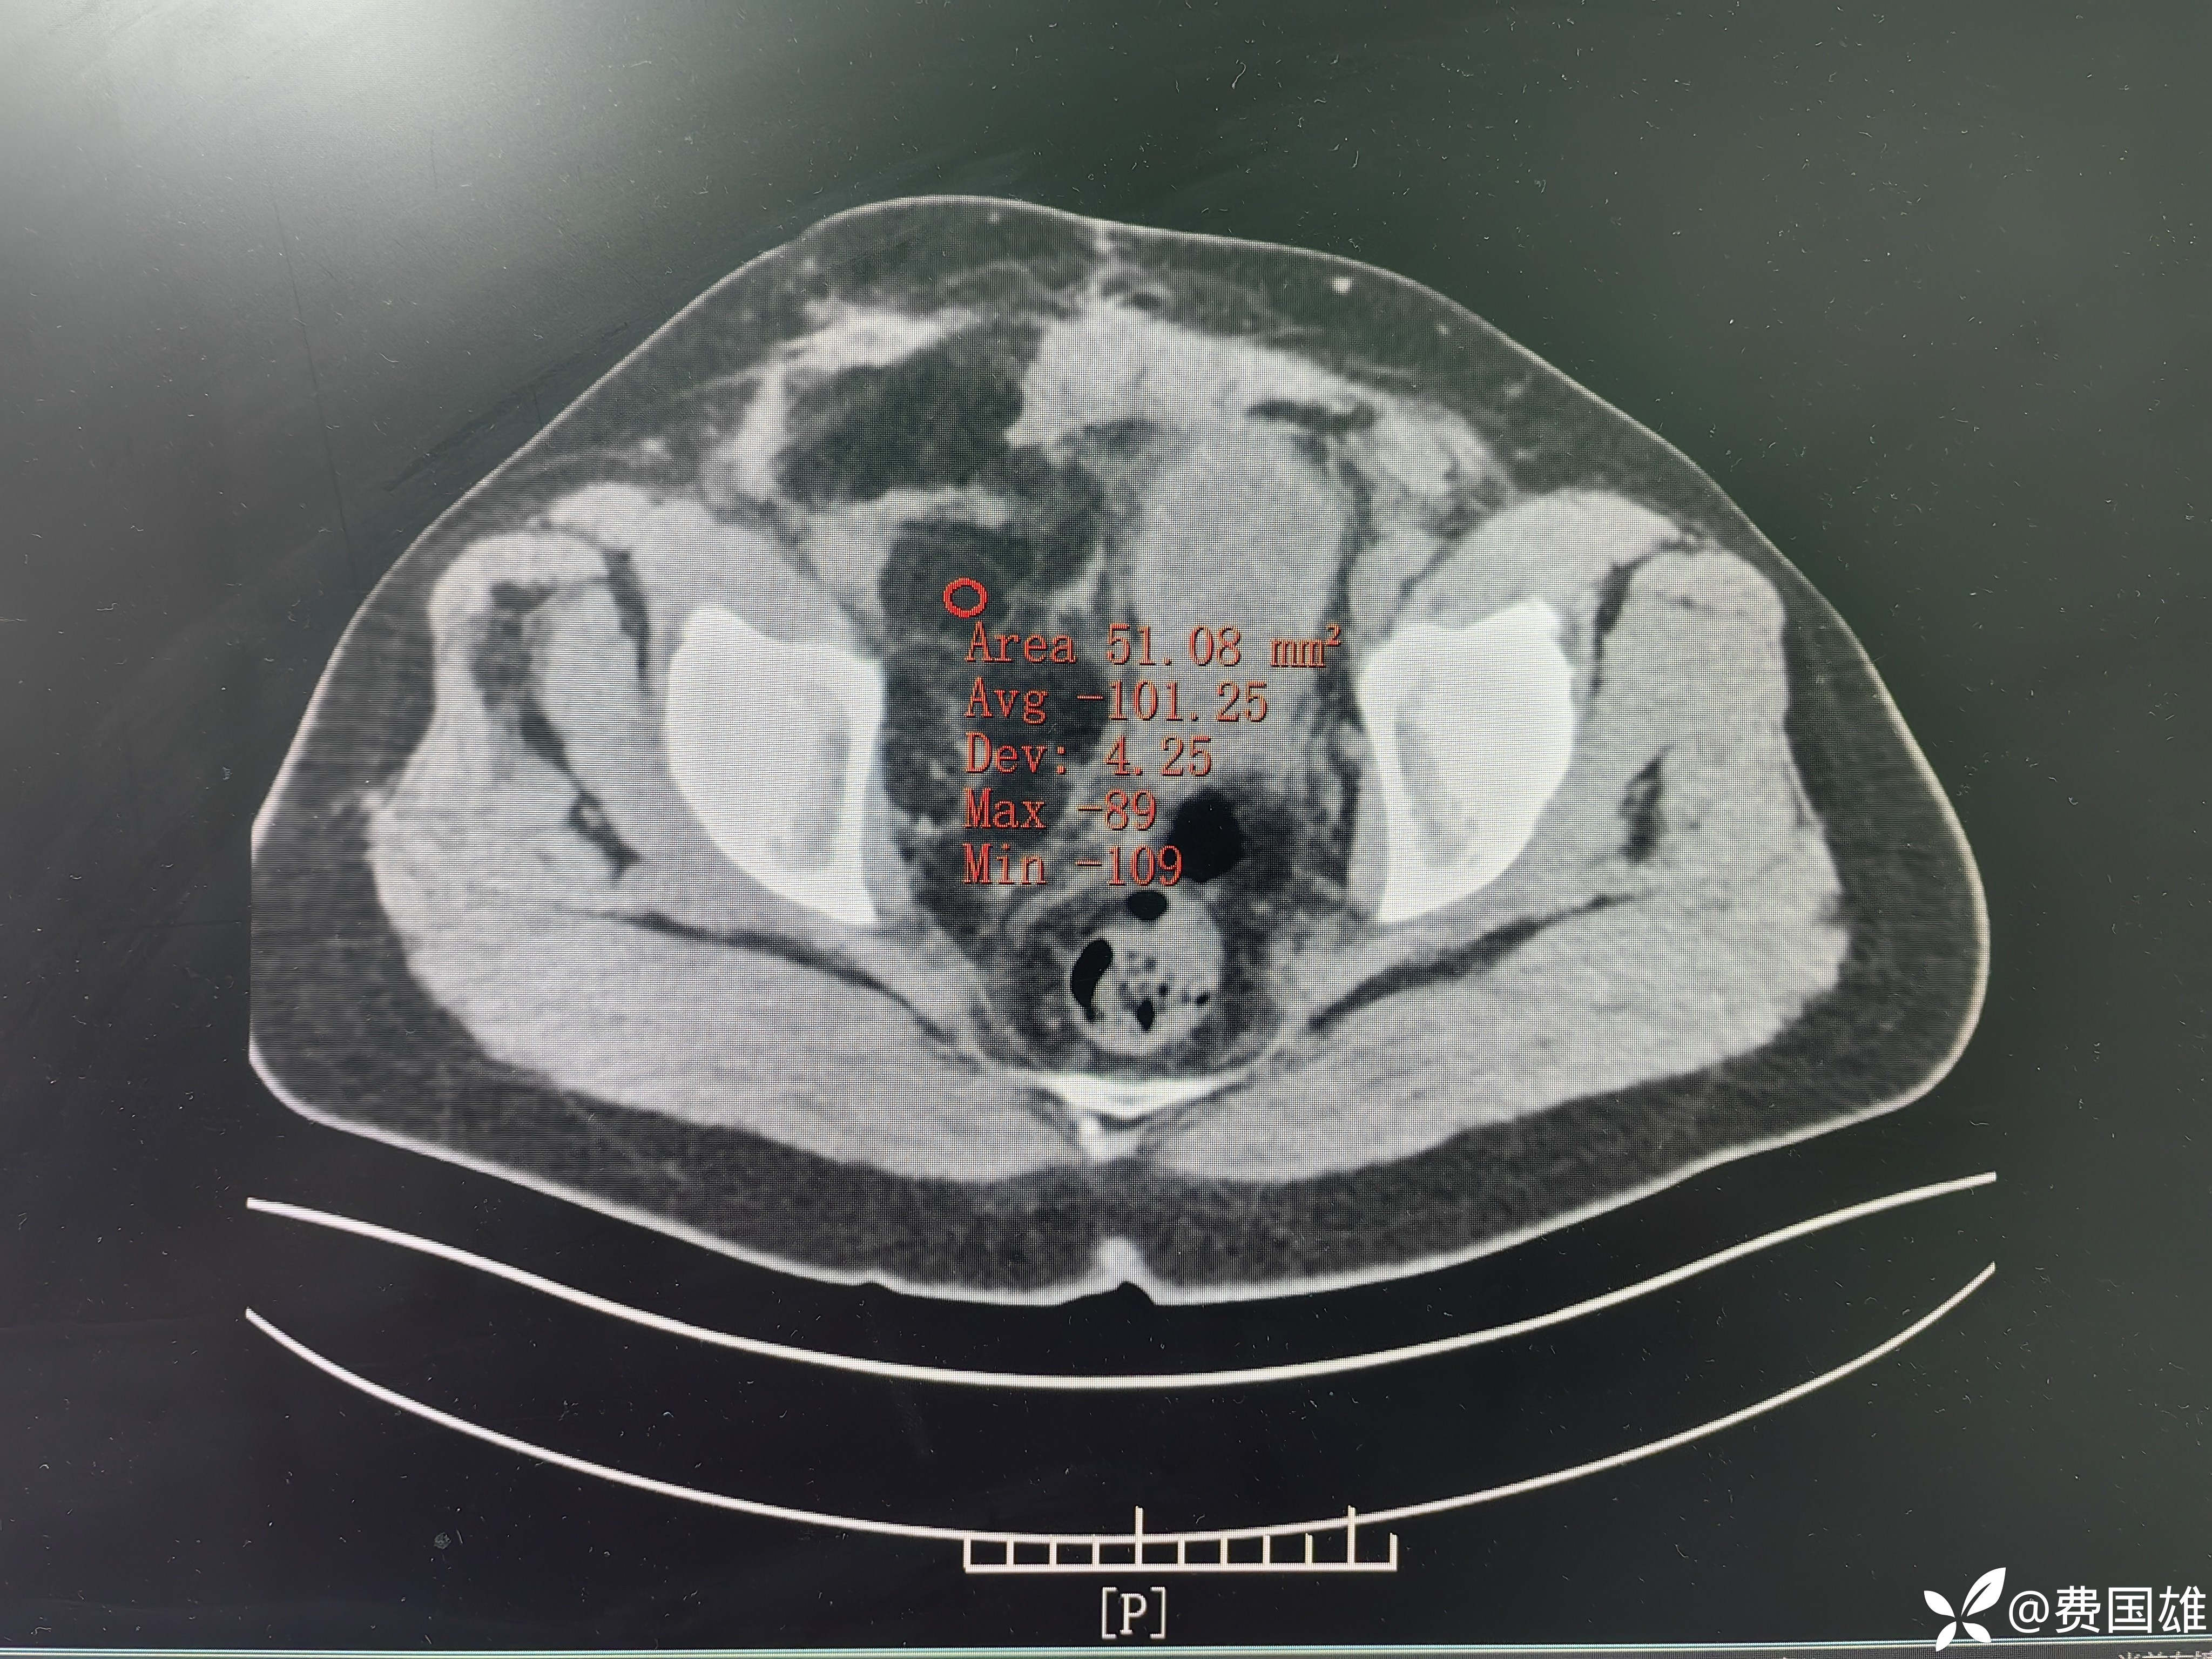

2024年复查腹盆腔+双下肢增强 CT 示:脂肪肉瘤术后,右侧盆腔至腹股沟区复发转移灶;右髋肌间隙复发灶。

第三次手术前盆腔CT